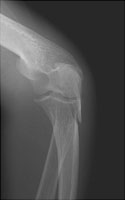

Olecranon Fracture

Olecranon fractures result from a direct fall onto a flexed elbow. As the triceps inserts upon the olecranon, most olecranon fractures tend to be displaced. These fractures are not generally comminuted.

- Click on the image for a larger versionBOblique radiograph of the elbow. This image also demonstrates the olecranon fracture.